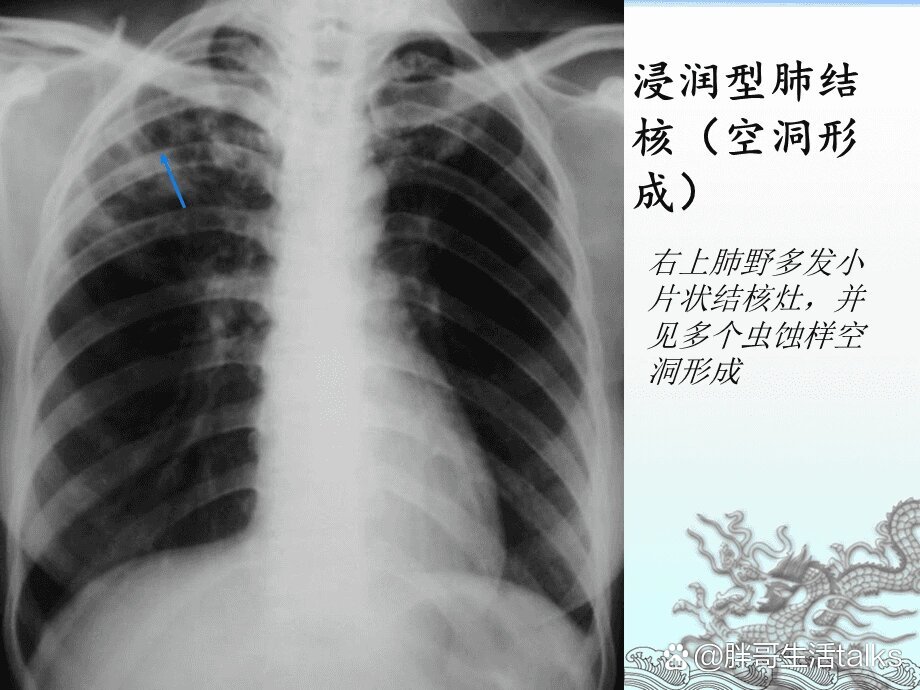

肺结核的影像学表现及鉴别诊断

肺结核的影像学表现及鉴别诊断

肺结核的影像学表现及鉴别诊断

肺结核的影像学表现及鉴别诊断

肺结核的影像学表现及鉴别诊断

肺结核的分型及影像学表现

肺结核的影像学表现及鉴别诊断